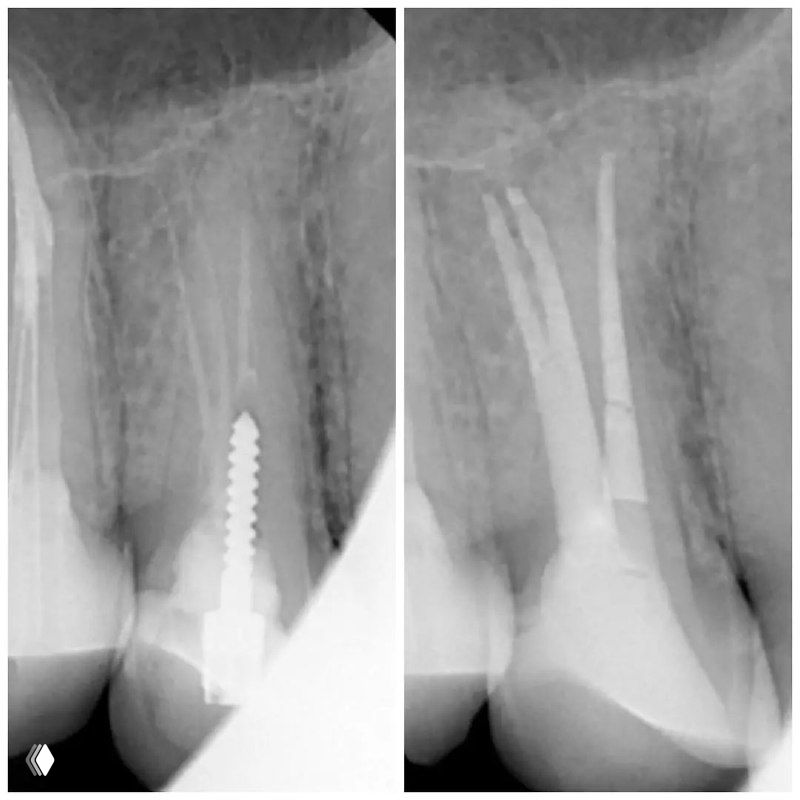

МТА — не просто "порошок". Это материал, который работает через 2 химические реакции. И если вы не понимаете механизм, то теряете эффективность.

- Реакция 1 - Гидратация. МТА + вода (из зуба и жидкости для замешивания) = гель

- Реакция 2 - Преципитация. Гидроксид кальция (в МТА) + гидроксиапатит (зуба) = химическая связь